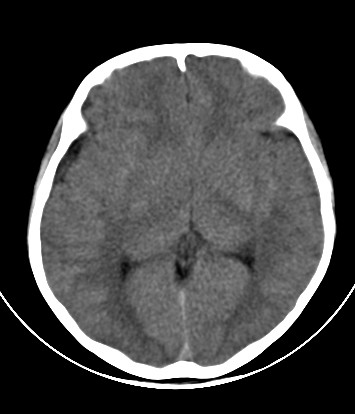

外伤一天,m,21y,骨窗示右颞骨骨折.

请大家看看,是脑内还是脑外(硬膜下还是硬膜外).请说说理由.谢谢.

右侧颞叶大片状形态不规则高密度影,边缘较模糊,无明显白质挤压移位。支持脑错裂伤、脑内血肿。

右侧颞叶大片状形态不规则高密度影,内缘较模糊,外缘紧贴颅板,无明显白质挤压移位伤。

依据:1.右侧颞叶不规则形血肿密度影,周围有水肿;

2.有明显占位效应;

3.颅板下硬膜下间隙存在。

右颞叶见混杂密度灶(以高密度灶为主)右侧脑室受压变形,中线结构左移,右颞部颅骨内板下见弧形高密度灶,右侧裂池及部分脑沟内见高密度灶;

结论:1:右颞叶脑挫裂伤;

2:右侧硬膜下血肿;

3:蛛网膜下腔出血。